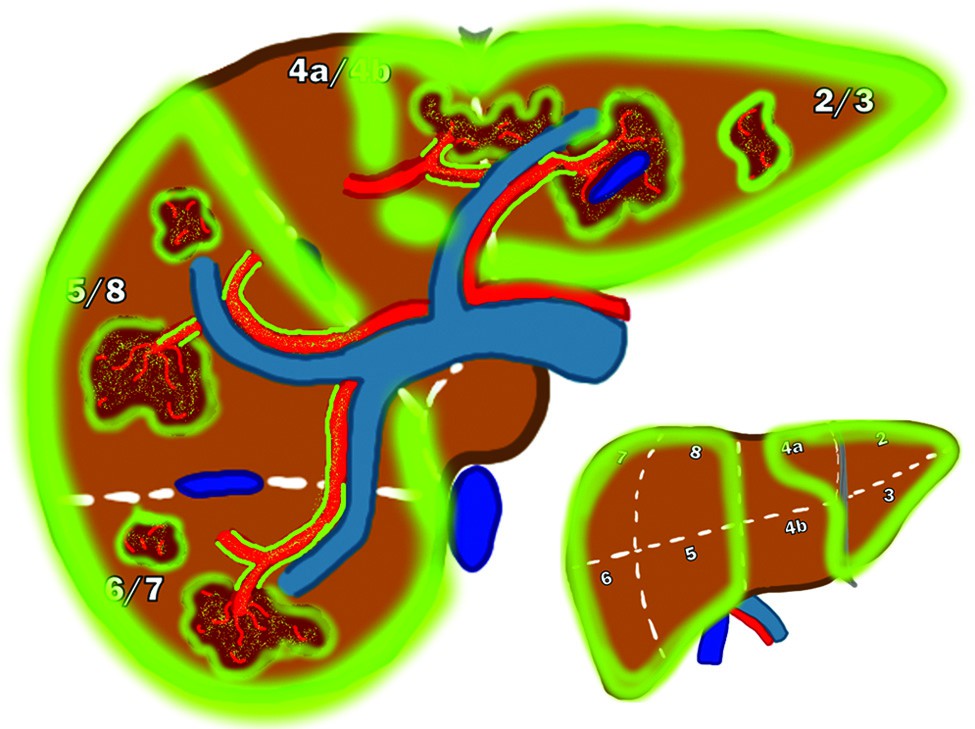

Segmentectomia con radioembolizzazione con ittrio-90 a base di resina (Y90-RE) con dosimetria secondo il Modello MIRD di un uomo di 72 anni con cirrosi da epatite C e un carcinoma epatocellulare (HCC) di 2,8 cm nel segmento 8.

(a) Immagine di Risonanza Magnetica (MRI) con soppressione del grasso in fase arteriosa T1 di una lesione epatica nel segmento 8. La punta di freccia bianca mostra il potenziamento del tumore.

(b) Cateterizzazione sotto-selettiva del ramo dell'arteria epatica che alimenta il tumore. La punta di freccia bianca mostra l'impregnazione (blush) del tumore con il mezzo di contrasto.

(c) Una Cone Beam CT (CBCT) "a secco" ha confermato una buona copertura del tumore al termine della procedura.

(d) La SPECT/CT fusa con tracciante di mappatura di tecnezio-99m macroaggregato (MAA) ha dimostrato un assorbimento soddisfacente nella lesione. Il volume del segmento 8 era di 197 mL. È stata presa la decisione di somministrare 27 mCi con microsfere di resina con 3 giorni di pre-calibrazione per raggiungere una dose di 250 Gy (Gray) all'angiosoma.

(e) Analisi dosimetrica post-trattamento tramite SPECT/CT di Bremsstrahlung di ittrio-90 con contorno del fegato normale (rosa) e contorno del tumore (rosso). La dose effettiva somministrata al tumore è risultata essere 472 Gy; la dose al fegato normale è stata di 37 Gy.

(f) Risonanza Magnetica (MRI) con soppressione del grasso in fase arteriosa T1 a 6 mesi dal trattamento. La punta di freccia bianca mostra una risposta completa nella zona del tumore. Le frecce bianche mostrano i cambiamenti post-trattamento nel parenchima epatico normale circostante.